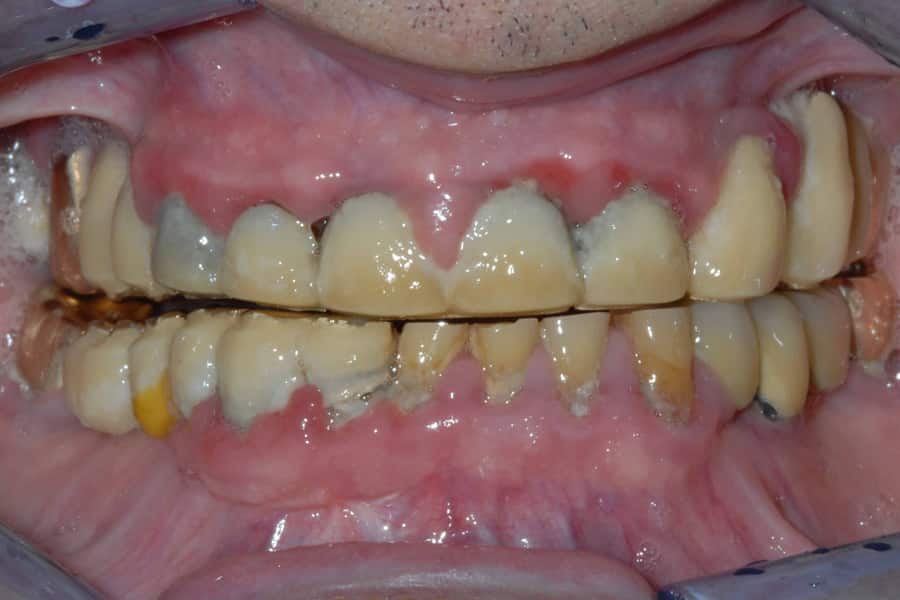

Un paziente cardiopatico si è presentato alla nostra osservazione con un quadro complicato da problemi sia di carie che di parodontite (piorrea).

La mobilità degli elementi dentari dovuti alla piorrea era evidente ed è stata progettata, per l’arcata superiore, una riabilitazione totale.

Sottolineiamo la situazione di partenza ed il risultato finale: